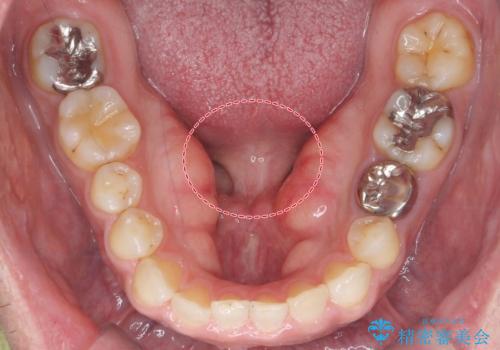

- 滑舌の悪さに長年悩まされており、意を決して手術での治療を希望し来院。

術前に舌の動きを確認した後、局所麻酔下での施術となりました。